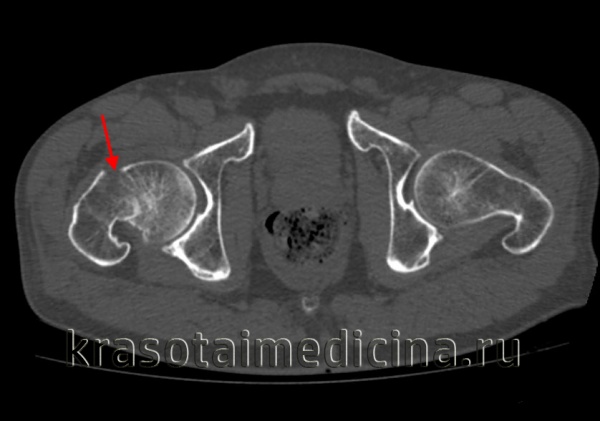

Класс А: перелом головки бедренной кости

Перелом головки бедренной кости встречается редко и может проявиться в сочетании с вывихом или без какой-либо значительной деформации. Его классифицируют по двум типам на основании размера и количества фрагментов. При переломах I типа имеется один фрагмент, в то время как переломы II типа являются оскольчатыми.

Для выявления этих переломов достаточно снимков тазобедренного сустава в обычных проекциях.